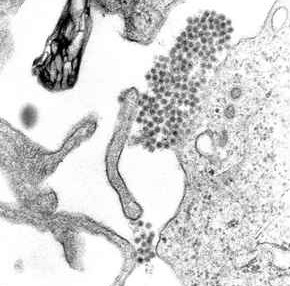

Virioni di Dengue virus visibili alla microscopia elettronica (sono il gruppetto di punti neri vicino al centro dell'immagine).